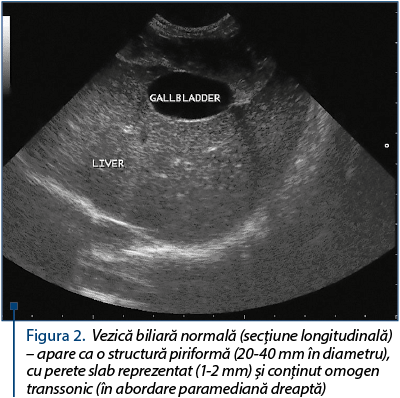

Aspectul ecografic normal al vezicii biliare – vezica biliară apare ca o formaţiune ovoidă anecogenă, perete fin-ecogen 2-3 mm şi cu diametru transversal de ≤4 cm (figura 1 şi figura 2).

Figura 2. Vezică biliară normală (secţiune lon­gi­tu­di­na­lă) – apare ca o structură piriformă (20-40 mm în diametru), cu perete slab reprezentat (1-2 mm) şi con­ţinut omogen transsonic (în abordare paramediană dreap­tă)

La pacienţii sănătoşi, vezica biliară este identificată uşor când pacientul este poziţionat în decubit lateral şi când sonda este direcţionată ventral, spre partea stângă. În mod normal, aspectul ei este hipoecogen, iar forma este ovoidă, cu un gât îngustat.